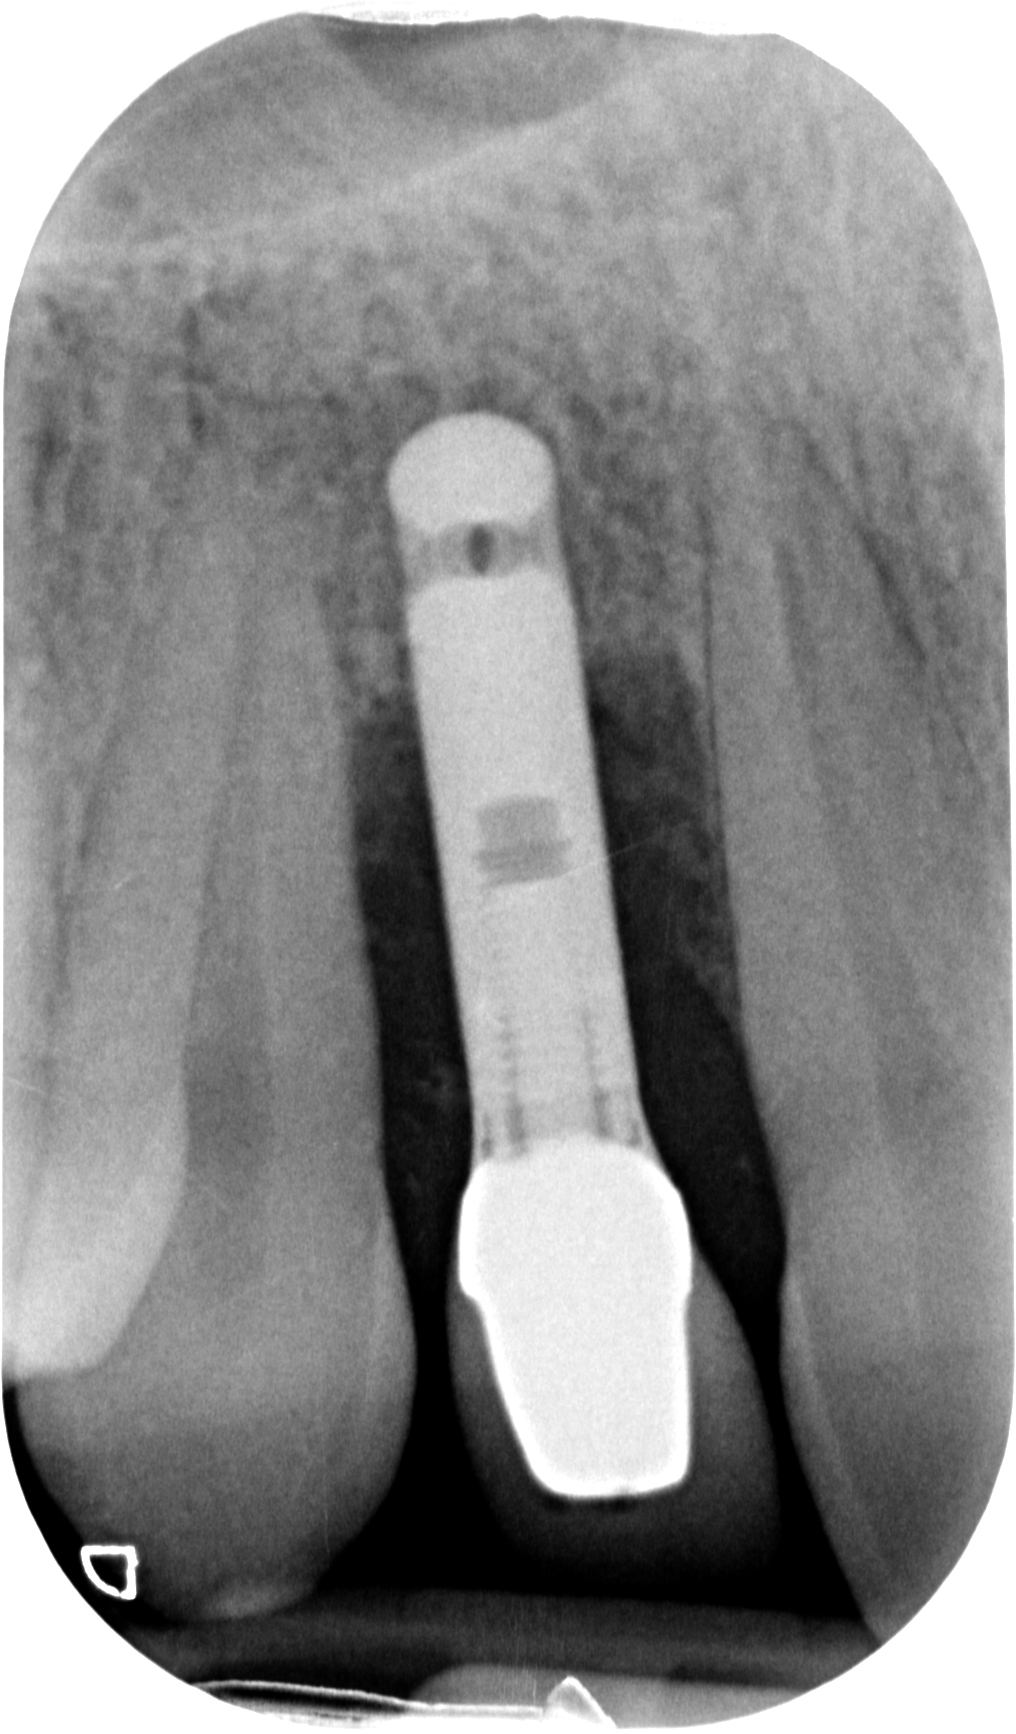

Ecco i risultati dei due casi:

DSC_0772

Sconosciuto-X-20170116-083502-XORTARNGADP-4

Nel secondo, ad esempio, un ponte non è paragonabile alla soluzione ricostruttiva che ho attuato. Neanche lontanamente! Quindi è inutile dire

“il ponte sarebbe stato meno invasivo”

Perché il ponte non era la terapia giusta in questo caso! PUNTO! Avrebbe richiesto un sacrificio biologico drammatico in una ragazza di 28 anni e avrebbe portato ad un estetica diciamo “discutibile” vista la mancanza di volume rosa residuata dopo la rimozione dell’impianto infetto.